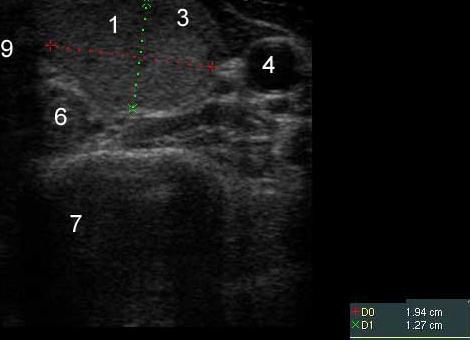

УЗИ щитовидной железы

Всем лицам с узловым зобом проводится УЗИ. При сравнительной дешевизне метода он несет в себе достаточную информационную нагрузку. Определяются параметры железы, размеры  и структура самих узлов, определяется кровоток, состояние лимфатических узлов. Имеются классические признаки злокачественности узлов.

Вероятностные признаки злокачественности узлов:

• Гипоэхогенный узел

• Единственный узел

• Узел в перешейке

• Неоднородный узел со множеством включений, кальцинатов, пристеночных тканей

• Неподвижность железы

• Усиленный кровоток в узле